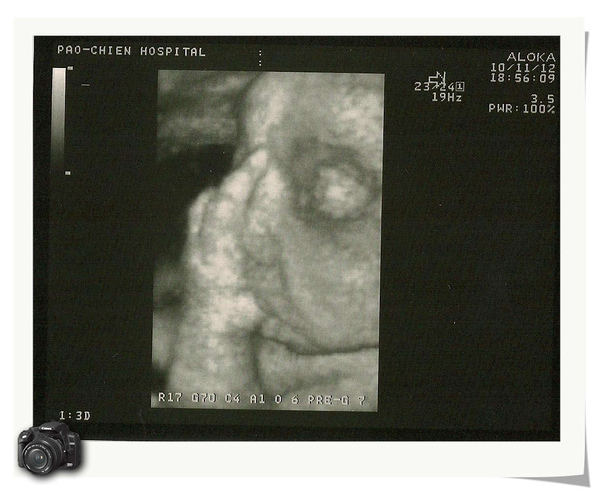

昨天去產檢,居然又比上星期胖了一公斤,我的天啊!小寶弟體重3500G,我該不會要生出巨嬰吧!醫生說應該下週就會生了,所以最後一週我要禁甜食、飲料了啦!我不想又要生一整天啦!!昨天拍的超音波超可愛的,小寶弟正在吸手指頭,從螢幕上看還看的到嘴巴一直在動咧!連醫生都一直笑,說這個小朋友有點愛吃唷!醫生還另外印出一張給外面的護士小姐看咧!連護士小姐都說好可愛唷!哈哈....

小寶弟正在吸手指頭小寶弟的大肚肚leaf0817 發表在 痞客邦 留言(0) 人氣(30)

小寶弟的肚子醫生說這張超音波是小寶弟在吃手指頭,看的出來嗎??ㄎㄎleaf0817 發表在 痞客邦 留言(0) 人氣(24)